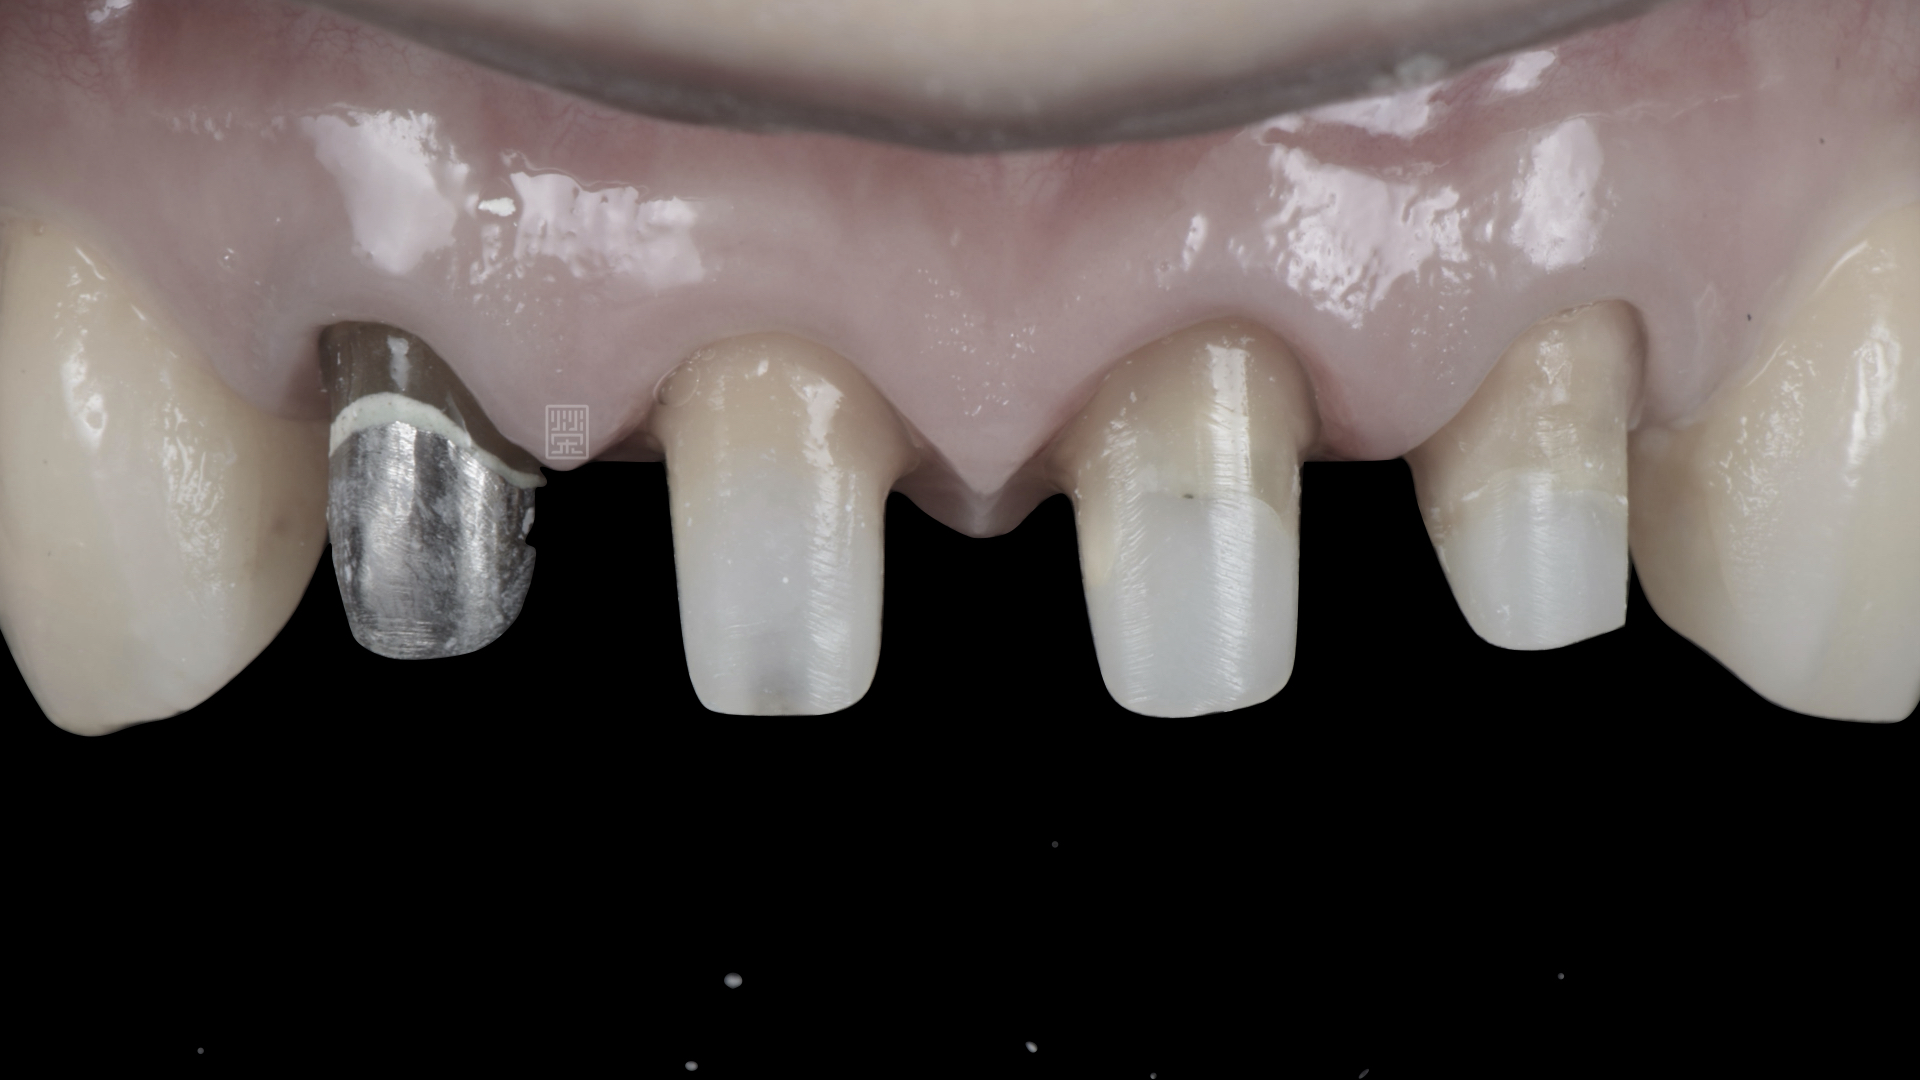

把邊緣放到牙齦下減少黑邊的產生